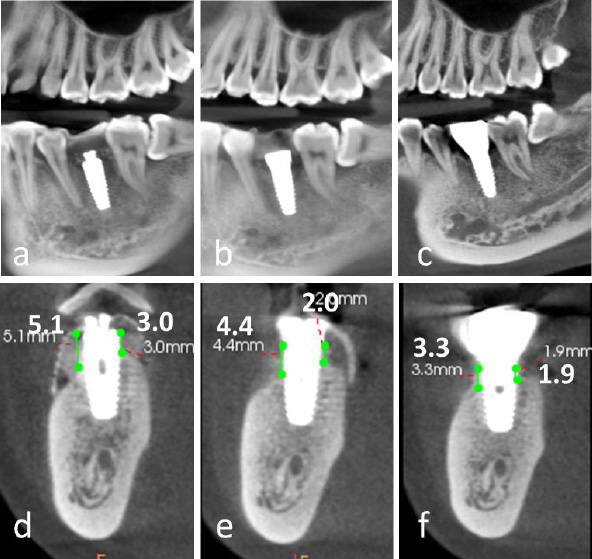

2.11. Alveolar Ridge Augmentation

A significant increase in both the width and height of the alveolar ridge was achieved. A transmucosal healing abutment was placed for two weeks, followed by the completion of a single-tooth implant restoration, resulting in satisfactory aesthetic and functional outcomes (Fig. 4d-4i). Postoperatively, the vertical bone height on the buccal side increased by 5.1 mm and on the lingual side by 3.0 mm (Fig. 5a-5f). Slight reductions in these measurements were observed upon completion of the implant restoration, with the buccal and lingual vertical bone heights measuring 4.4 mm and 2.0 mm, respectively (Fig. 5b, 5e).

At the 2.5-year follow-up, the vertical bone height on the buccal side was maintained at 3.3 mm, while the lingual side measured 1.9 mm (Fig. 5c, 5f).

Comparative analysis of cone-beam computed tomography (CBCT) imaging at different treatment stages. (a-c) Panoramic reconstructed views: (a) Immediate postoperative evaluation, (b) Healing abutment placement phase, (c) 2.5-year follow-up after prosthetic delivery, (d-f) Cross-sectional views corresponding to respective treatment phases, (d) Postoperative implant positioning, (e) Peri-implant tissue maturation during healing phase, (f) Long-term (2.5-year) evaluation of peri-implant bone stability and prosthetic integration.